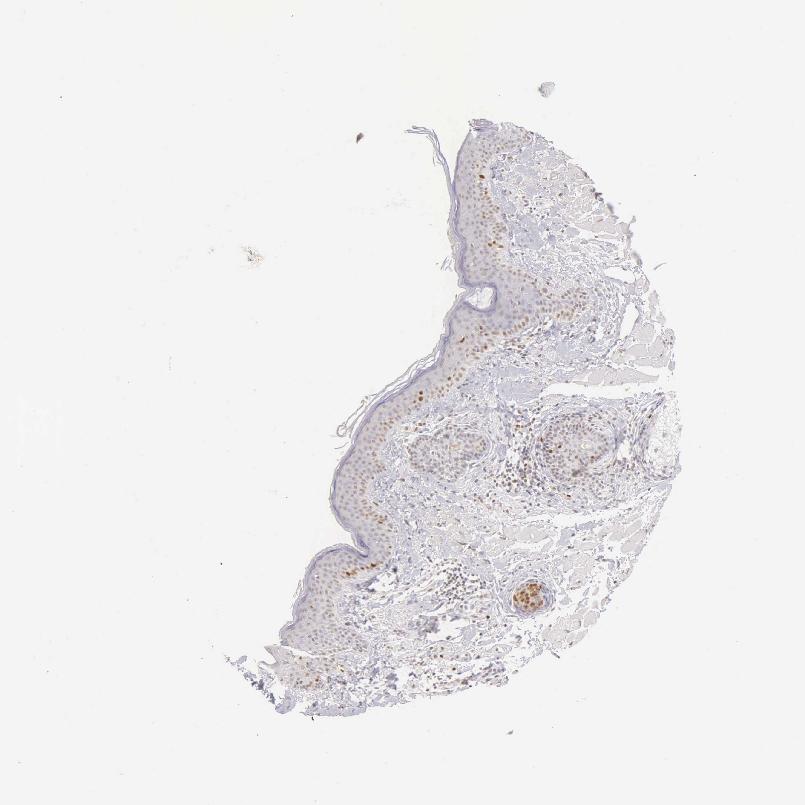

SKIN 1 - Antibody stainingi

Antibody staining in the annotated cell types in the current human tissue is reported as not detected, low, medium, or high, based on conventional immunohistochemistry profiling in selected tissues. This score is based on the combination of the staining intensity and fraction of stained cells.

Each image is clickable and will lead to virtual microscopy that enables deeper exploration of all samples and also displays staining intensity scores, fraction scores and subcellular localization as well as patient and tissue information for each sample.

Antibody HPA000451Antibody HPA001164Antibody CAB000058Antibody CAB068198Antibody CAB080228

Langerhans Not detectedMedium-Not detectedNot detected

Cells in basal layer --Medium--

Cells in corneal layer --Not detected--

Cells in granular layer --Not detected--

Cells in spinous layer --Medium--

Endothelial cells --Not detected--

Extracellular matrix --Not detected--

Fibroblasts MediumNot detected-Not detectedNot detected

Fibrohistiocytic cells --Not detected--

Hair follicles --High--

Keratinocytes MediumMedium-LowMedium

Langerhans cells --Not detected--

Lymphocytes --High--

Melanocytes LowNot detectedNot detectedNot detectedNot detected

Sebaceous glands --Medium--

Vascular mural cells --Not detected--